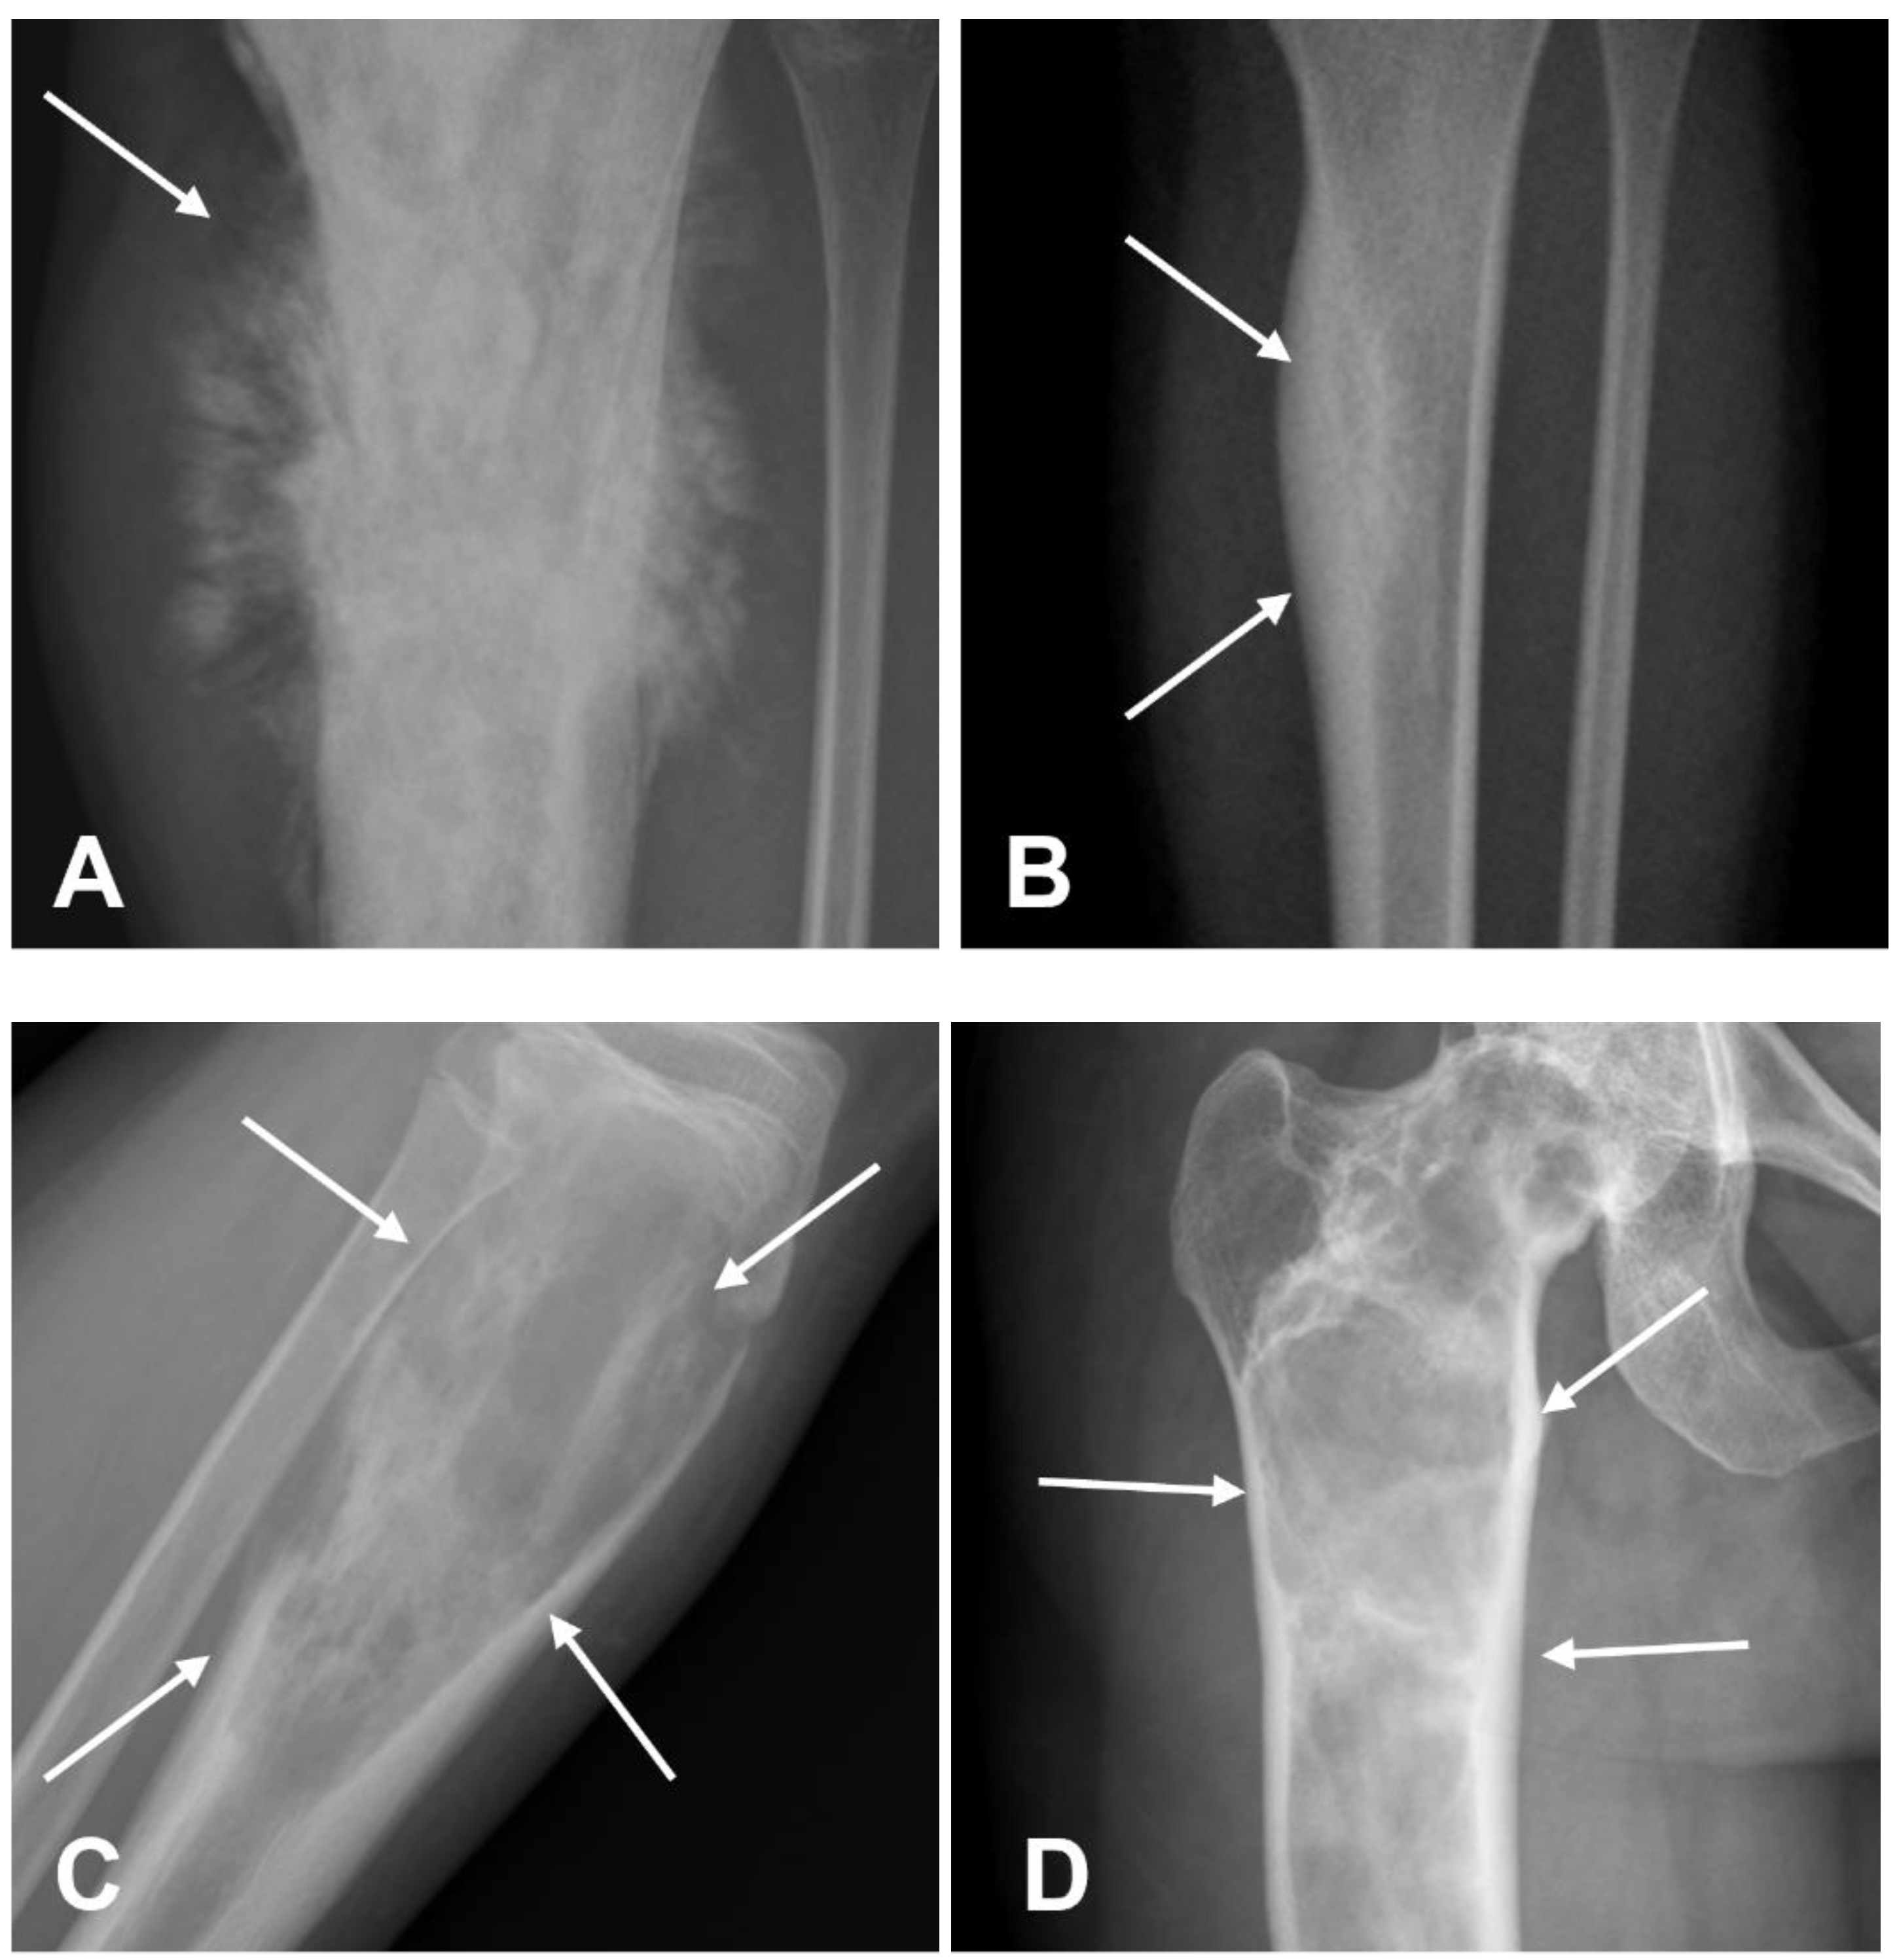

3.1.1. Conventional Osteosarcoma

- Murphey, M.D.; Robbin, M.R.; McRae, G.A.; Flemming, D.J.; Temple, H.T.; Kransdorf, M.J. The Many Faces of Osteosarcoma. RadioGraphics 1997, 17, 1205–1231. [Google Scholar] [CrossRef] [PubMed]